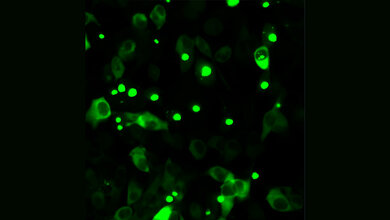

Um diese in menschlichen Nervenzellen von Huntington-Patientinnen und -Patienten aufzudecken, schloss sich ein interdisziplinäres Team aus den Bereichen Neurologie, Neurowissenschaft und Bioinformatik der Molekularen Neurologie und der Stammzellbiologie des Uniklinikums Erlangen zusammen. Mittels induzierter pluripotenter Stammzellen, die aus Hautzellen von Menschen gewonnen und anschließend in ein frühes Zellentwicklungsstadium versetzt werden, wurden im Labor Gehirnnervenzellen hergestellt. Das Team behandelte diese Nervenzellen von Huntington-Betroffenen mit Branaplam und entdeckte, dass sich das schädliche Huntingtin bereits nach Zugabe geringster Wirkstoffmengen verringerte.

Im Vorfeld war bereits bekannt, dass Branaplam sich an RNA-Botenmoleküle bindet. Um aufzuklären, welche Effekte der Wirkstoff auf die RNA-Botenmoleküle hat, wurde die Gesamtheit aller RNA-Moleküle in vielen Zellreihen mittels RNA-Sequenzierung gemessen. Dr. Florian Krach aus der Erlanger Stammzellbiologie gelang es mittels biostatistischer Verfahren und auf Basis künstlicher Intelligenz, den Wirkmechanismus in dieser enormen Datenmenge zu entschlüsseln: Demnach hat Branaplam einen bedeutenden Effekt auf das sogenannte Spleißen von RNA-Biomolekülen. Dabei werden nicht benötige Abschnitte der RNA-Botenmoleküle entfernt. Dies wird ebenfalls beim RNA-Botenmolekül des Huntingtin-Gens beobachtet. Der nicht herausgeschnittene Abschnitt in der Huntingtin-RNA führt dazu, dass das RNA-Botenmolekül instabil und infolgedessen abgebaut wird – somit kann das genetisch veränderte Huntingtin gar nicht erst entstehen.